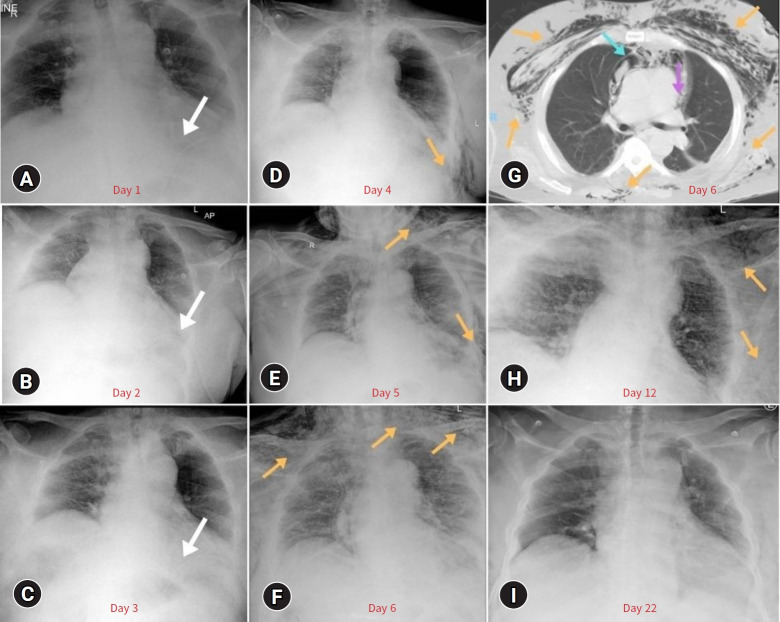

Pneumomediastinum is an uncommon complication in cases of blunt chest trauma but can signal severe underlying issues. This report discusses a 69-year-old male patient with preexisting conditions of obesity, sleep apnea, and asthma, who experienced delayed pneumomediastinum and pneumopericardium following the removal of a chest tube. This tube had been placed to address a traumatic hemopneumothorax, which had resolved. The removal of the chest tube triggered a series of events, exacerbated by the patient's chronic health conditions. The patient was managed conservatively with close monitoring and physiotherapy, which successfully resolved the condition without the need for further invasive procedures. The multifactorial nature of the Macklin effect illustrates that even routine procedures such as chest tube removal can trigger a chain reaction in susceptible patients. The choice of conservative management, rather than immediate invasive interventions, underscores the delicate balance necessary in trauma care.